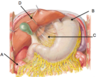

Label A-D

A: hepatic flexure

B: fundus

C: lesser omentum

D: falciform ligament